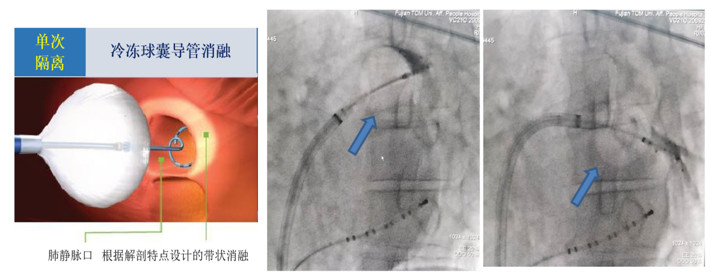

房颤冷冻球囊导管消融